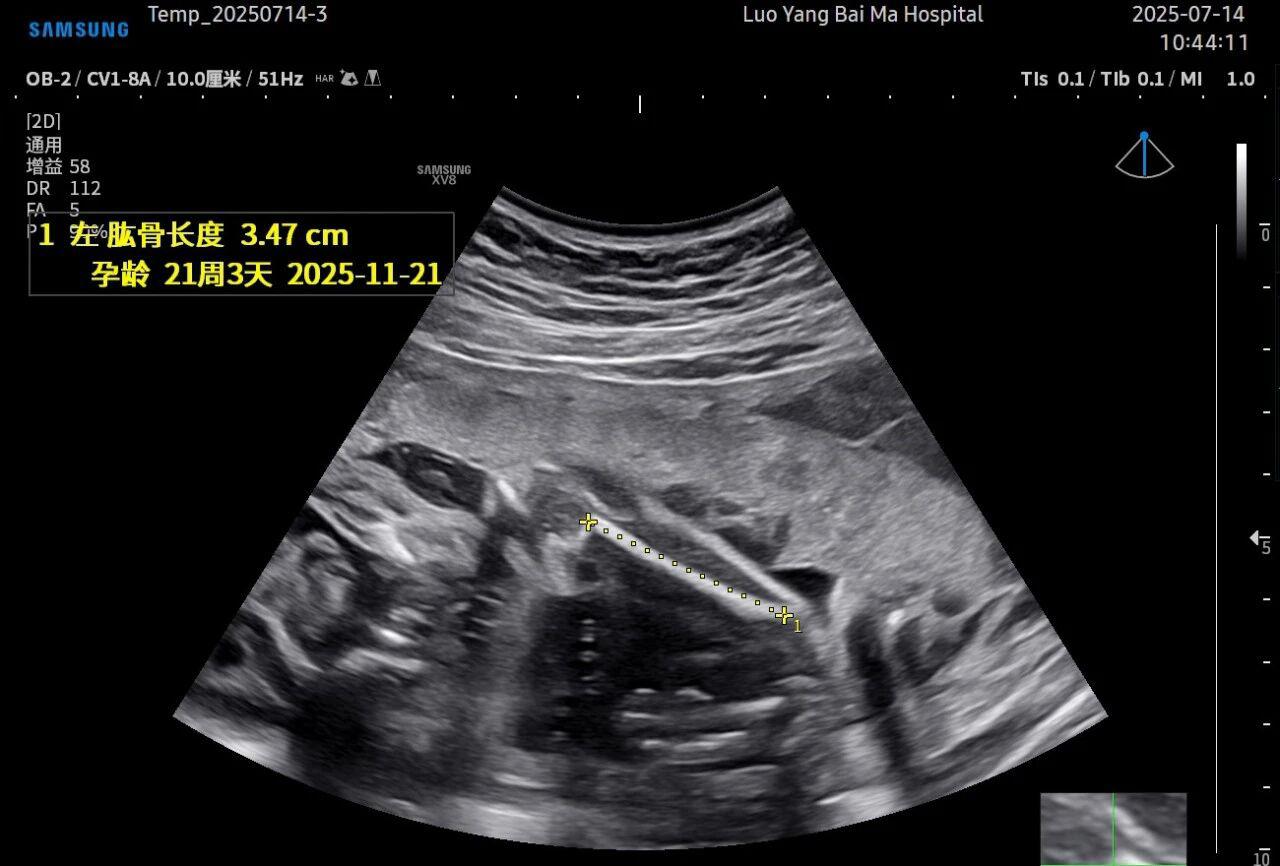

这是5D技术的核心优势之一。系统内置了强大的智能化大数据分析功能和AI辅助诊断工具。例如,在进行胎儿颈项透明层(NT)测量、胎儿长骨(LB)测量等关键生物学指标评估时,5D智能系统可以自动识别解剖层面、智能勾勒测量范围并进行计算。这不仅大大缩短了检查时间,更重要的是,它通过标准化的智能算法减少了因人为操作可能产生的误差,使诊断结果更加客观、可靠。